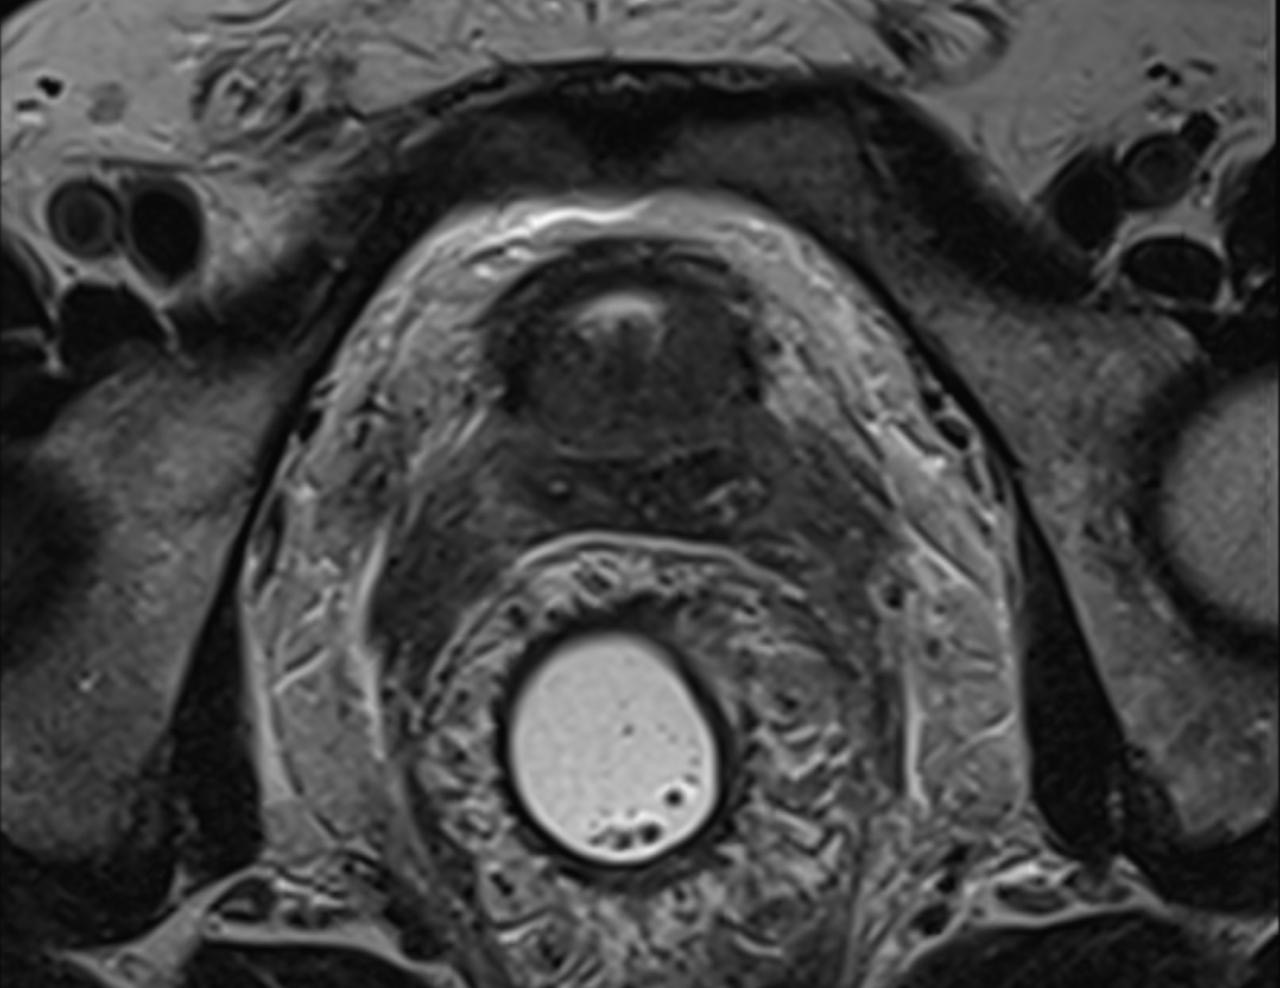

T1- weighted MRI, mass involving anterior wall of rectum